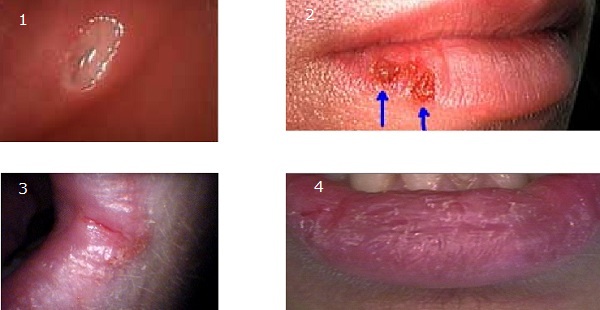

Oral Herpes

Lesions in the oral cavity that are painful, red, and ulcerative can result from oral herpes.

HSV-1 is the most common cause of oral herpes.

HSV-2 can also cause oral herpes.

The initial oral herpes infection typically strikes children and preteens.

The herpes virus remains dormant in the trigeminal nerve ganglia after the initial sores have healed.

Stressors like tension, heat, sunlight, etc. can make the herpes virus reactivate.

The red pimples and ulcers return when the virus is reactivated.

Leukoplakia

A frequent premalignant lesion of the mucous membranes of the mouth, throat, larynx, esophagus, and genitalia is called leukoplakia, sometimes known as white patch disease.

A white spot on the tissue’s surface that cannot be removed is the hallmark of leukoplakia.

Usually, neither bleeding nor ulcers occur in leukoplakia.

Erythroplakia

Erythroplakia is a red plaque that is a tissue lesion characterized by thickened epithelial mucosa with areas of white plaques.

Erythroplakia is also known as vascularized leukoplakias.

Red plaques are associated with oral cancer.

Erythroplakia usually occurs on the gingiva, buccal mucosa, lateral tongue surface, floor of mouth or retromolar trigone.

These lesions are most commonly found on the anterior surface of the maxillary alveolar ridge, but they have been reported to arise on the hard palate, vestibular sulcus and soft palate.